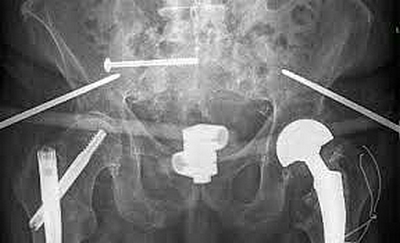

Unlike younger patients... older adults can sustain pelvic fractures from something as simple as losing their balance and landing on their side.